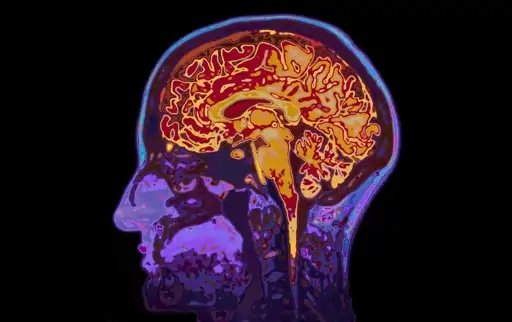

En concreto, los investigadores documentaron que los observadores experimentados presentan una estructura de tejido mucho más densa y compleja. Estas modificaciones se localizan en regiones cerebrales estrechamente vinculadas con la atención y la percepción visual. Para localizarlas, realizaron resonancias magnéticas sobre 58 sujetos, 29 de ellos expertos en la observación de aves y otros 29 que nunca habían realizado esta actividad. Para garantizar la fiabilidad de los resultados, todos ellos estaban equiparados en edad y nivel educativo.

El neurocientífico Erik Wing, autor principal de la investigación, explicó los resultados obtenidos de la siguiente manera: “La medida que utilizamos es la difusión de las moléculas de agua en el cerebro. Una forma sencilla de explicar este fenómeno es que hay menos restricciones sobre dónde va el agua en los cerebros de los expertos”.

Los datos sugieren que el cerebro de los expertos ha experimentado una especie de actualización del sistema que mejora el rendimiento cognitivo de forma selectiva. Cuando los participantes se enfrentaron a imágenes de aves desconocidas, las áreas optimizadas se activaron con intensidad para facilitar la identificación. Este fenómeno refuerza la teoría de la neuroplasticidad, donde el esfuerzo mental moldea físicamente el órgano.